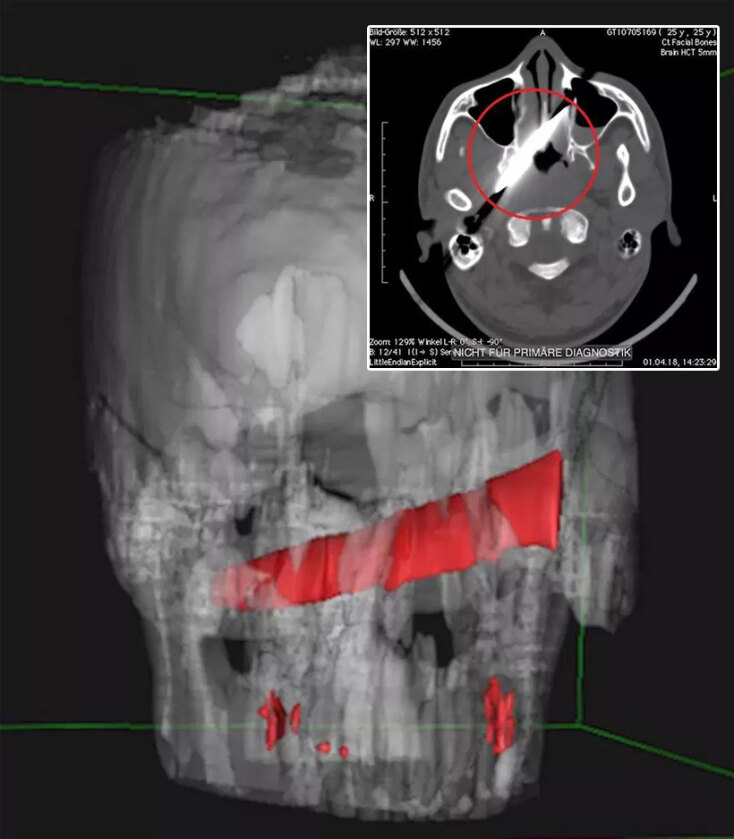

Δεν μπορούσαν να πιστέψουν αυτό που έβλεπαν οι γιατροί που κλήθηκαν να αντιμετωπίσουν περιστατικό με μαχαίρωμα στη Νότια Αφρική. Οι ακτινογραφίες του κρανίου προκάλεσαν ανατριχίλα.

Μια λεπίδα, μήκους 10 εκατοστών, ήταν καρφωμένη κάτω από το αριστερό μάτι ενός 25χρονου. Η λαβή του μαχαιριού είχε σπάσει, με τη λεπίδα να έχει σφηνωθεί βαθιά σε οστό του κρανίου. Ο 25χρονος τραυματίστηκε σοβαρά κατά τη διάρκεια ενός καβγά με φίλο του, ενώ και οι δύο βρίσκονταν υπό την επήρεια αλκοόλ. Όπως ανέφερε σε δηλώσεις του, μετά τον καβγά πήγε για ύπνο και ξέχασε τι είχε συμβεί, ξυπνώντας στη συνέχεια με έντονους πονοκεφάλους και με οξύ πόνο κάθε φορά που κουνούσε το αριστερό του μάτι.

Θορυβημένος, πήγε σε κλινική του Γκέρμιστον (ανατολικά του Γιοχάνσεμπουργκ) για ακτινογραφίες. Τα αποτελέσματα σήμαναν συναγερμό.

Κρίθηκε απαραίτητη η μεταφορά του σε άλλο νοσοκομείο, το Chris Hani Baragwanath Academic Hospital, στη συνοικία Σοβέτο του Γιοχάνσεμπουργκ, όπου πραγματοποιήθηκαν διαδοχικές συσκέψεις με τη συμμετοχή νευροχειρούργων, γναθοχειρούργων και χειρούργων οφθαλμίατρων, καθώς η περίπτωση του 25χρονου ήταν εξαιρετικά σπάνια.

Το καλό νέο ήταν ότι η λεπίδα δεν είχε προκαλέσει ρήξη μεγάλων αιμοφόρων αγγείων. Το χειρουργείο έγινε τέσσερις ημέρες μετά τον τραυματισμό του άνδρα, με το αιχμηρό αντικείμενο να αφαιρείται με επιτυχία.